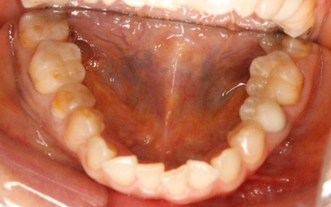

一見すると、下の前歯に多少の凸凹があるものの、そんなに目立って歯並びが悪いわけではないので、患者様も噛み合わせに問題があるとは思っていませんでした。

しかし、よく観察してみると、右下の奥歯が異常に削れているのがわかります。

上の写真のように、象牙質と呼ばれる第二層目(歯の内面の黄色い部分)が露出していますが、これは異常なことです。ちなみに、外側の第一層目はエナメル質です。

人間の歯は1年間で約0.03mmしか咬耗しないと言われており、エナメル質自体も厚みが2mm以上ある人が大半です。つまり、まだ50歳の段階で歯の内面が露出するほど削れてしまっているというのは、何か特別な要因が潜んでいることが考えられます。